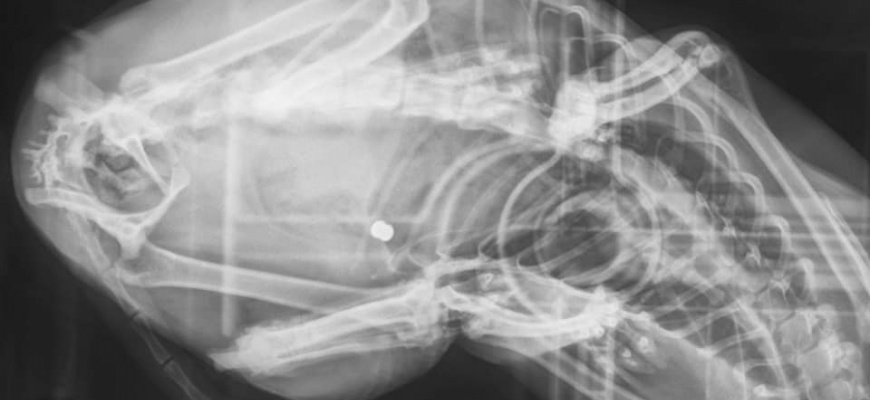

"Witam wszystkich posiadaczy i nie posiadaczy zwierzęcych przyjaciół. Pisze, aby ostrzec Was przed człowiekiem, który z przyczyn, których pojąć nie potrafię, strzela do bezbronnych zwierząt. Wczoraj tj. 27.04, zauważyłam, że moja kotka dziwnie się zachowuje, wygląda jakoś "nieswojo", widać było po niej również, że chodzenie jak i siedzenie sprawia jej trudność oraz ból. Na ciele znalazłam ranę, początkowo przypuszczałam, że to efekt walk terytorialnych z innymi kotami, atak jakiegoś psa lub niefortunne zahaczenie się jej o coś, przykładowo siatkę ogrodzeniową. Po wizycie u lekarza weterynarii, który stwierdził, że rana jest dokładnie jak po postrzale z.......WIATRÓWKI (!!!), zdjęcia RTG tylko to potwierdziły.